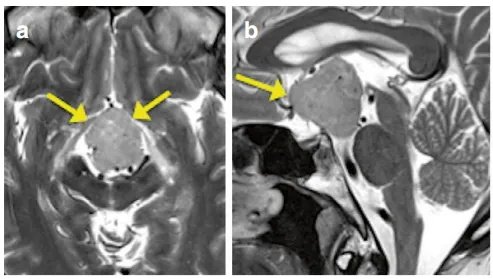

但是医生让我做头部检查,直到我做了MRI检查,答案才残酷地摆在面前:我的脑子里长了一个肿瘤。医生指着MRI图像(图a、b)告诉我,这个鞍上肿瘤已经压迫到了关键的大脑区域——向脚间池延伸并致中脑大脑脚受压变形。

术后MRI证实肿瘤已肉眼全切(图d、e)。